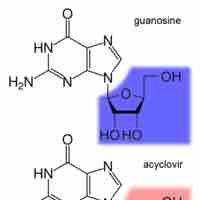

Inhibiting DNA synthesis during viral replication is another key approach in battling viral infections.

Reverse transcriptase in viruses is inhibited by nucleoside (nucleotide) analogues or drugs that change the conformation of the enzyme.